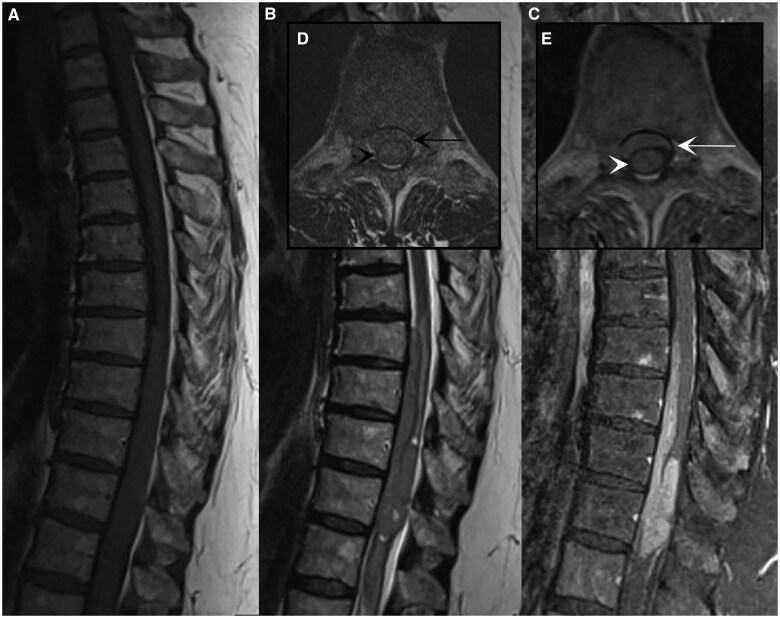

Primary melanomas of the spinal meninges are exceedingly rare. While both intramedullary and extramedullary spinal melanomas have been reported, to the best of our knowledge, this is the first noted case of primary spinal melanoma that has both intramedullary and intradural extramedullary components. We present a case of a 61-year-old female presenting with a 1-year history of lower back pain, bilateral lower extremity pain, and perceived weakness of left foot. Magnetic resonance imaging of the thoracic spine suggested intramedullary and intradural extramedullary mass at levels T8-T12. A T7-T12 laminectomy with resection of the spinal cord mass revealed a pathological diagnosis of primary meningeal melanoma. This case highlights the complexity of diagnosing spinal melanomas, which often mimic more common spinal tumours such as ependymomas, astrocytomas, metastasis, or lymphoma. Often meningeal melanomas require extensive imaging and clinical evaluation to exclude other sites of potential primary melanoma. This case adds to the sparse literature by documenting a rare manifestation and could provide valuable insights into the diagnosis and management of similar cases.